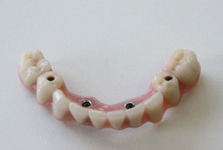

Pevné můstky – lepené nebo šroubované

Třmeny

Kulové attachmenty

Sub-Tec Locator®

Protetické řešení může být pomocí můstku, který je kotvený na implantátech nebo pomocí jednotlivých korunek na implantátech.

V zásadě je možné do těchto můstků zařadit i přirozené zuby, zejména pokud je potřeba tyto zuby ošetřit proteticky - korunkami. Korunky nebo můstky mohou být na implantáty nacementovány nebo přišroubovány.